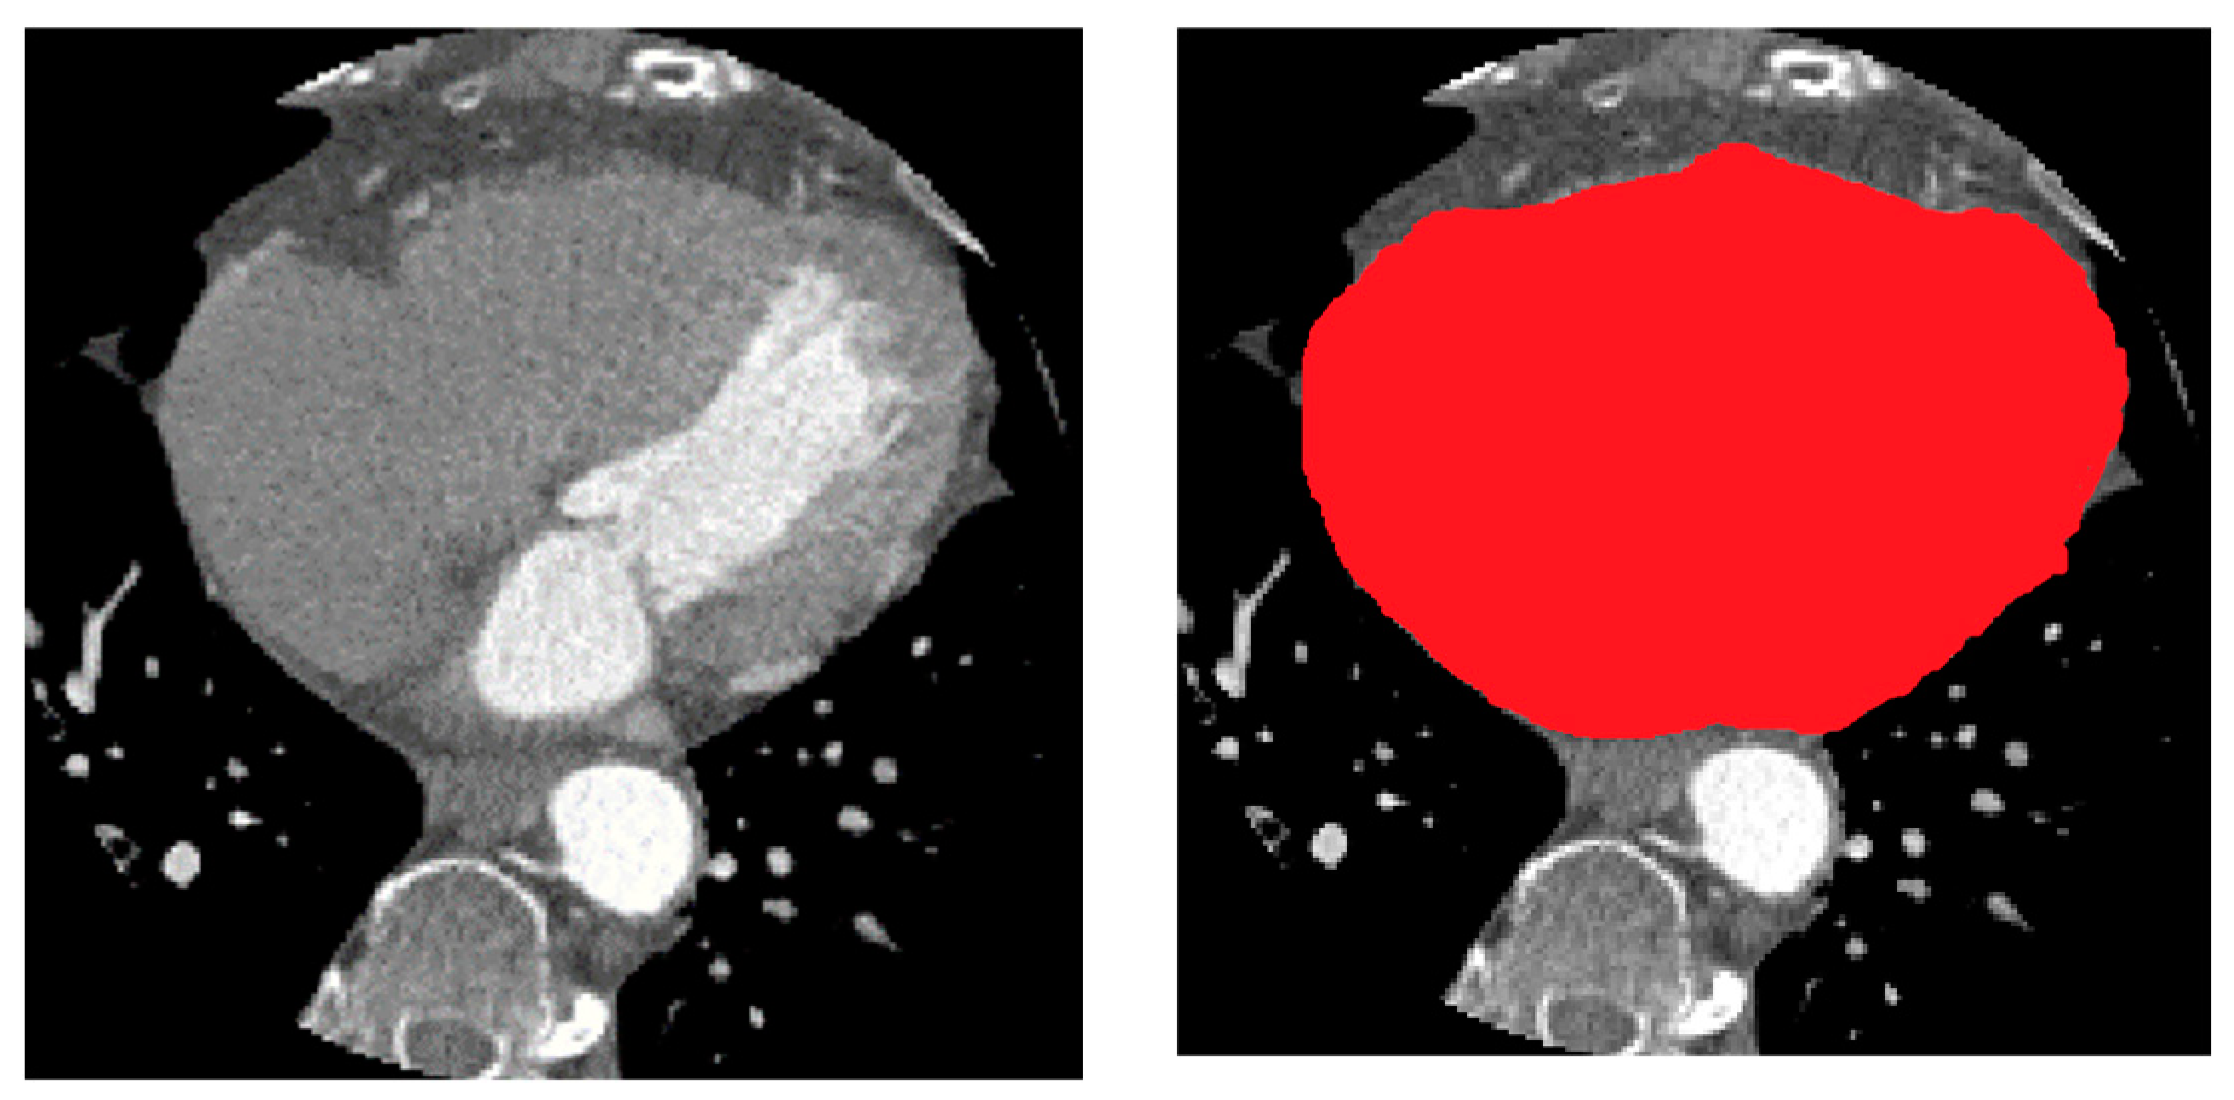

The high DSC score of 0.98 suggests that the ResUNet model was able to accurately identify and delineate the heart region within the CTA images. This is a significant achievement as the heart is a complex structure surrounded by other organs and tissues, making its segmentation a challenging task. The high DSC score demonstrates the model’s ability to capture the intricate details and boundaries of the heart, ensuring that the segmentation closely matches the ground truth. An example of the segmented heart (red color) in a CTA image is shown in Figure 7.

For other measures values, the Recall metric of 0.99 indicates that the model was able to identify almost all of the heart region, with only a negligible proportion of the heart organ being missed. This is a crucial aspect, as it ensures that the model is not overlooking important anatomical features that could be crucial for the next stage of segmenting the coronary arteries. The high Recall score suggests that the model is highly sensitive in detecting the heart region, which is particularly important in the next stage of segmenting the coronary arteries where missing critical information could have negative consequences. Furthermore, the Precision metric of 0.99 indicates that the model’s predictions were highly accurate, with a low rate of false positive detections. This means that the model was able to distinguish the heart region from the surrounding tissues and structures with a high degree of certainty.

Figure 7. Example of heart segmentation from target CTA.

Bioengineering 11 00759 g007